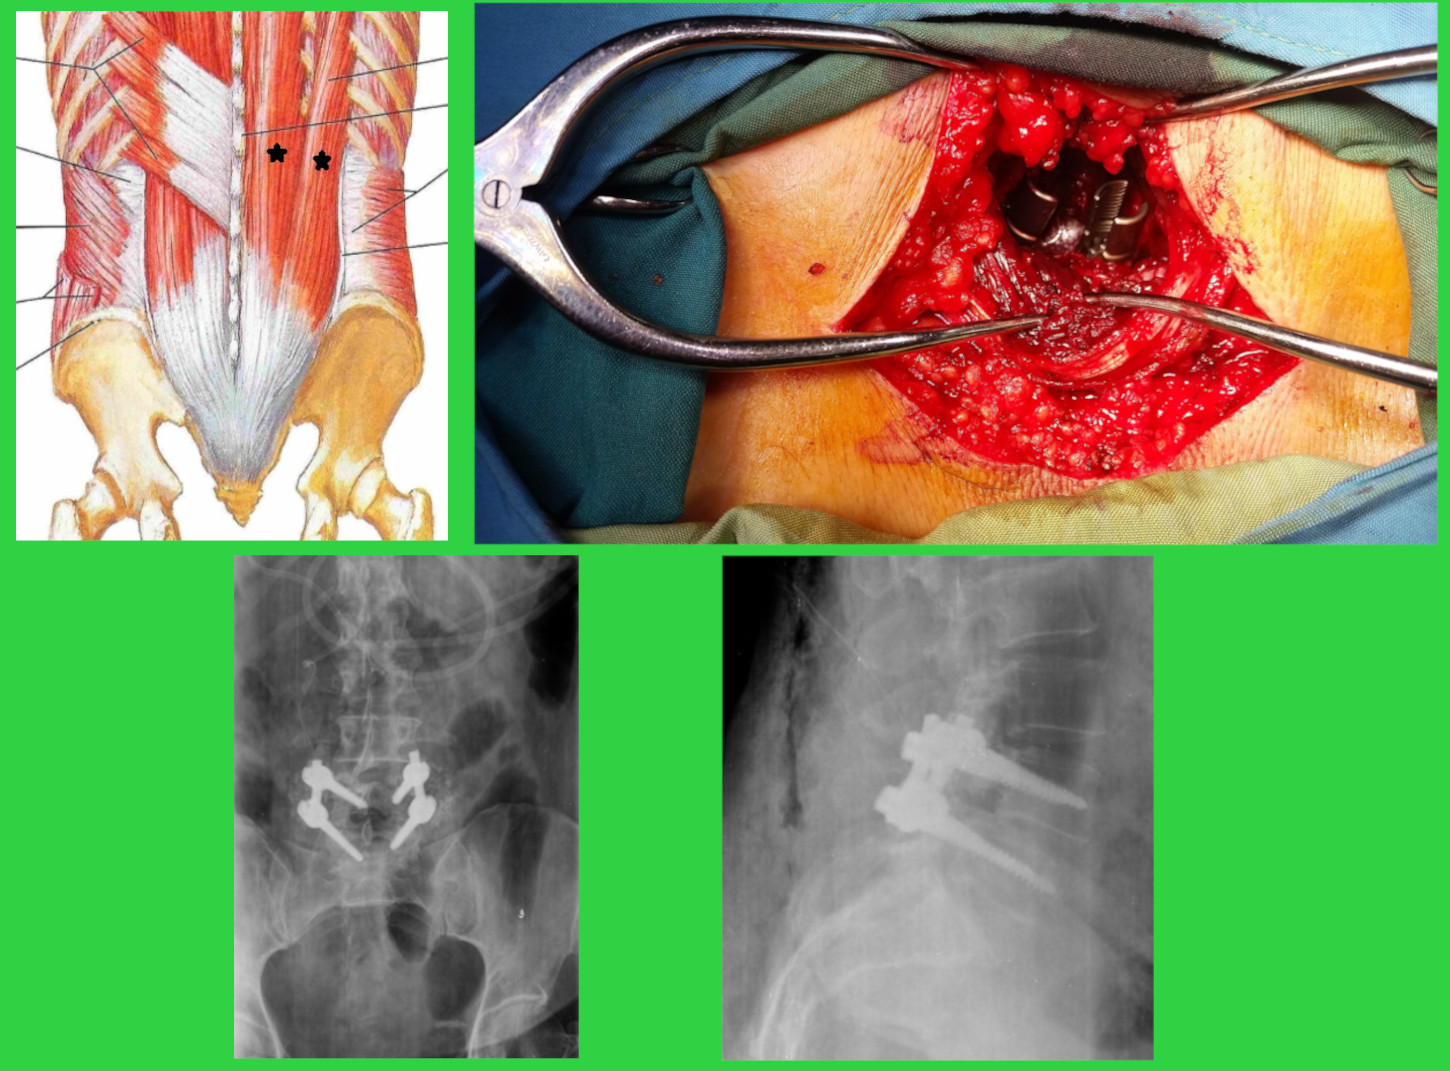

تصاویر بالا مربوط به بیماری است که لغزندگی مهره (اسپوندیلولیستزیس) داشته است. در درمان این بیمار یک عمل با روش جدید انجام داده ایم. در این روش از بین دو ماهیچه اصلی کمر وارد میشیم و اصلاً خود مهره دستکاری یا باز نمی شود. در شکل بالا سمت چپ دو ماهیچه را با علامت ستاره مشکی نشان داده ایم. لیگامان ها و ساختمان های پشت مهره اصلاً دستکاری نمی شوند. عکس بالا سمت راست عکس حین عمل را نشان می دهد که دو پیچ گذاشته شده در مهره را می بینید. این دوپیچ از بین ماهیچه ها گذاشته شده است. عکسهای پایینی عکسهای رادیوگرافی پس از عمل بیمار می باشند.